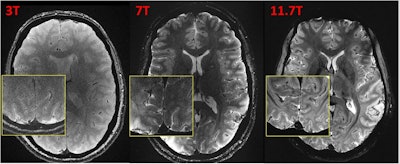

In one experiment, the group imaged three subjects using three different MRI scanners configured with exactly the same parameters and compared the images. The differences are clear, and it’s a “no brainer” that 11.7 tesla reveals superb brain details, Boulant said.

Caption: T2*-weighted 2D GRE acquisitions at 3T, 7T, and 11.7T (different volunteers). Sequence parameters : FA = 27°, TR = 600 ms, TE = 20 ms, resolution = 0.2 × 0.2 × 1 mm3, GRAPPA = 2, bandwidth = 40 Hz/px, TA = 4 min 20 s. Acquisitions were performed with 1 (body coil) Tx-32Rx, 8Tx-32Rx, and 8Tx-32Rx head coils at 3T, 7T, and 11.7T respectively.Image courtesy of Nicolas Boulant, PhD